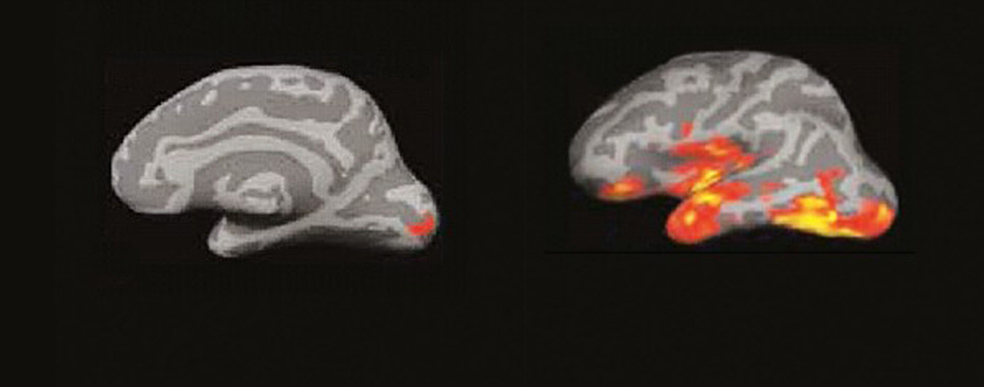

El cerebro del lector: un incendio de ideas

La imagen por resonancia magnética del cerebro de alguien que lee muestra algo parecido a un incendio forestal en un día de viento. Las pavesas vuelan y prenden nuevos conatos en diferentes zonas…

Entre 100 y 170 milisegundos. (A la izquierda) 1. Cuando leemos, cada palabra que ve nuestra retina produce un eco en la corteza cerebral. La primera señal eléctrica se aprecia en el polo occipital. (A la derecha) 2. La actividad se extiende a la región temporal izquierda, donde está el buzón del lenguaje, que aísla la forma visual de la palabra y la reconoce.